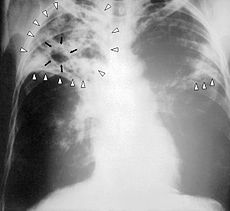

По решению суда больного можно продержать в медицинском учреждении до трех месяцев, однако, в случае обоснованной врачом необходимости, этот термин может быть продлен. В законопроекте также присутствует пункт, разрешающий вносить данные о больных туберкулезом в специализированный реестр. Стоит отметить, что эпидемия этого заболевания была объявлена на территории Украины ещё в 1995 году.

Украинцев больных туберкулезом будут лечить насильно